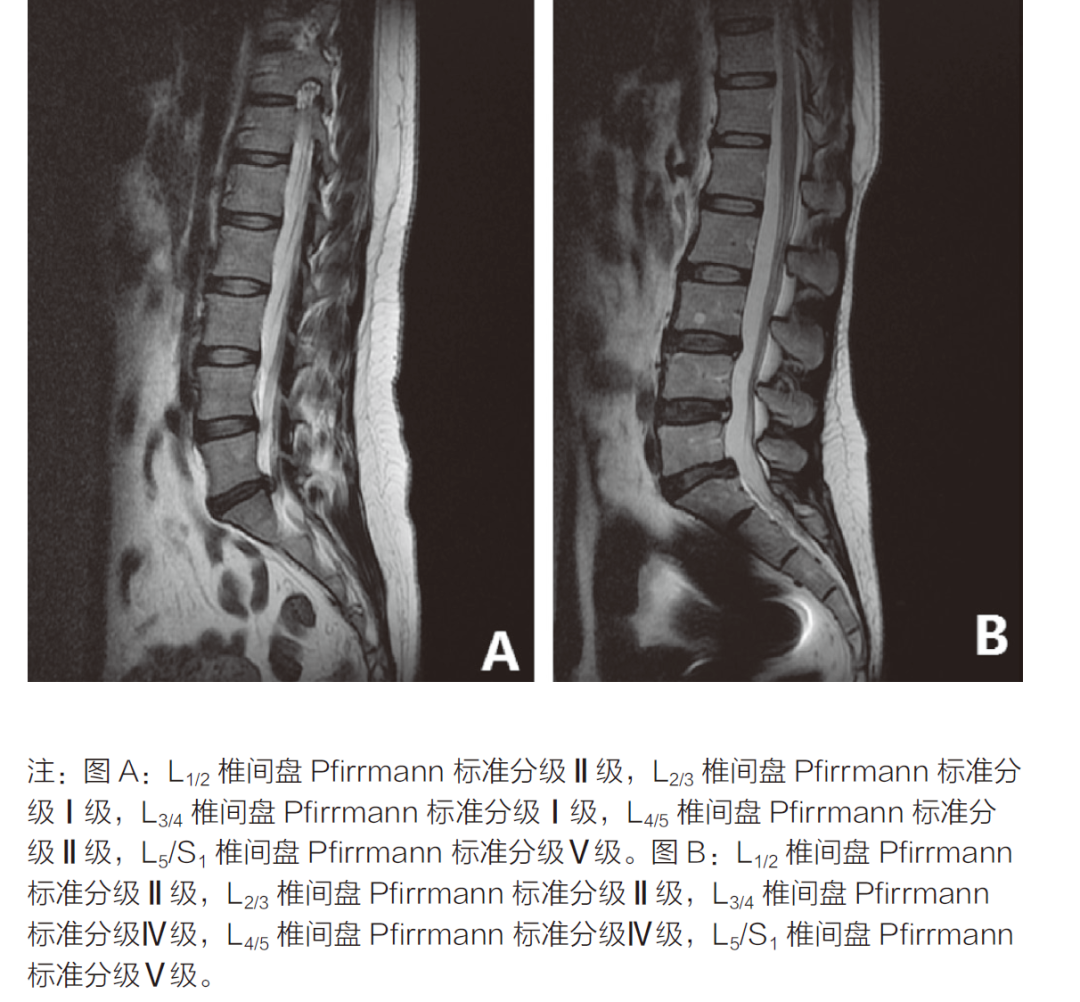

腰椎间盘退变分级常用 pfirrmann 分级,根据腰椎间盘在 T2 序列上信号减低程度及形态变化分为 1 ~ 5 级。

III 级:椎间盘的结构不均匀,呈不均匀的中等信号强度,核与环之间界限不清楚,椎间盘高度正常或轻度塌陷。

IV 级:椎间盘结构不均匀,呈低信号的深灰色信号强度。核和环之间的界限消失,椎间盘高度正常或中度塌陷。

V 级:椎间盘结构不均匀,黑色低信号,髓核与纤维环之间的界限消失,椎间盘重度塌陷。

椎间盘退变 pfirrmann 分级,图示 A ~ E 依次为 I ~ V 级的 T2 矢状位图像,图源:DOI:10.1097/00007632-200109010-00011

图源:DOI:10.3969/j.issn.1674-9308.2019.12.031